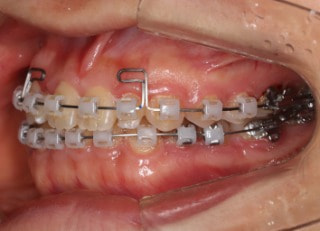

治療法:フルパッシブブラケット:T21

治療開始時

治療開始から25ヶ月後